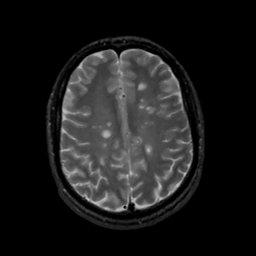

MR Study #1, February 10, 1991 -- Slice #35